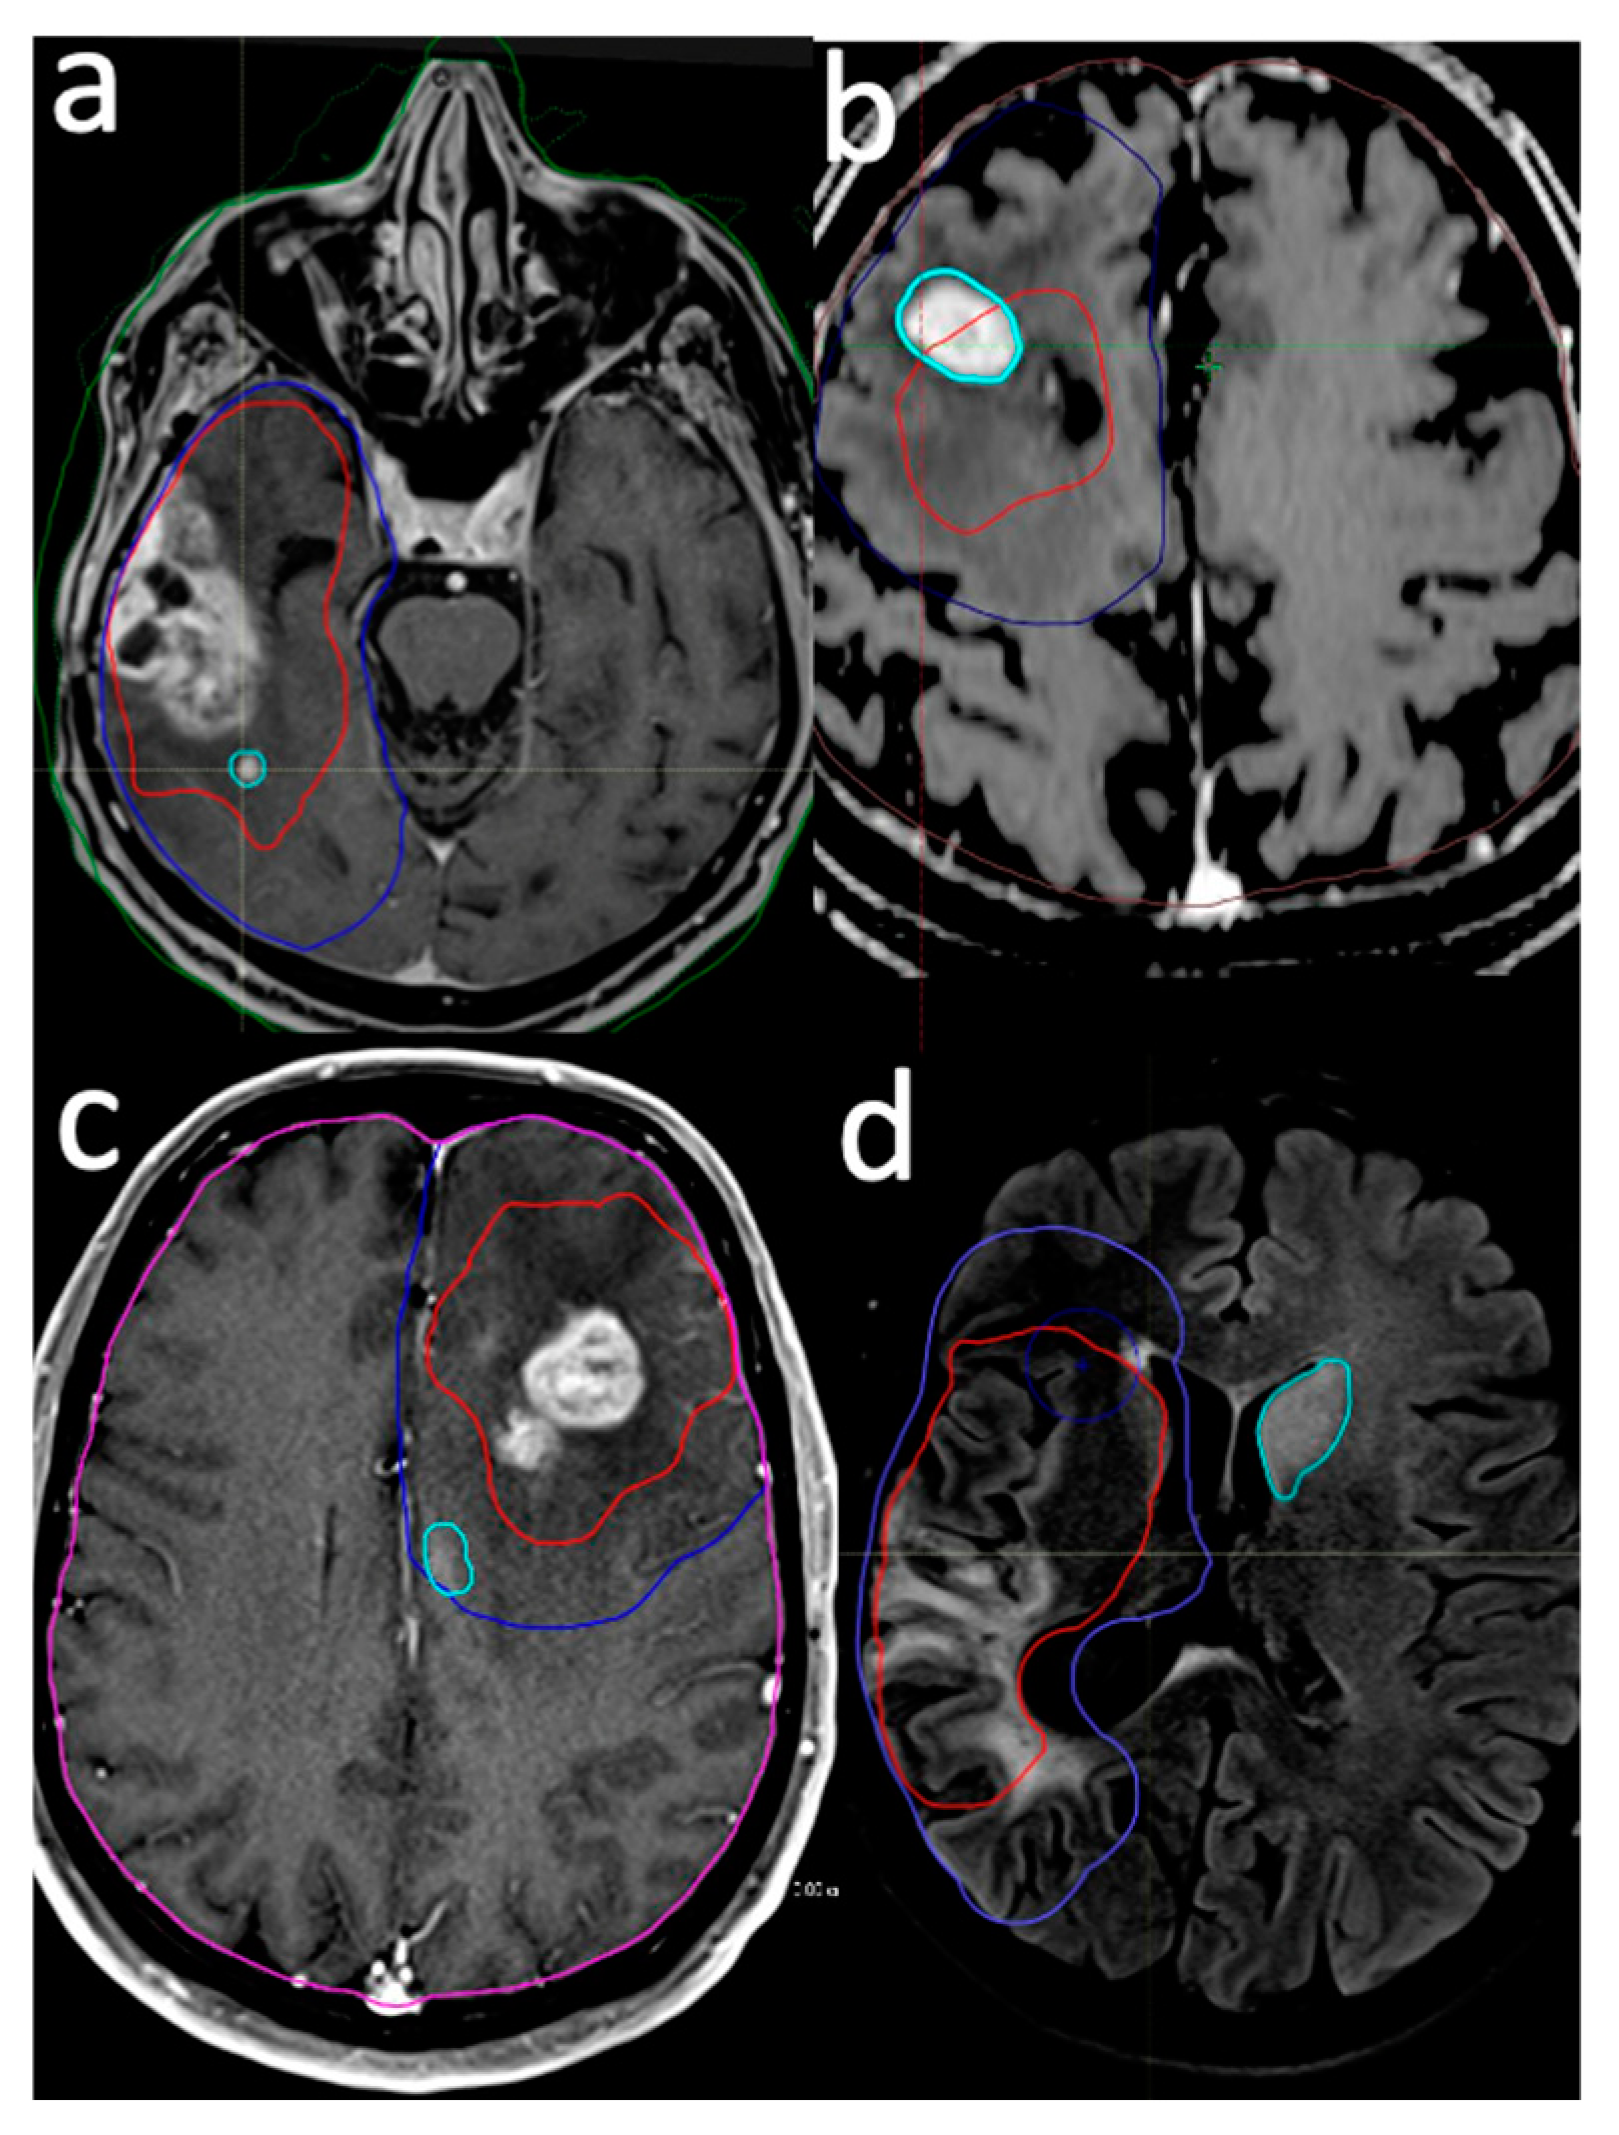

Patients underwent initial MRI scans six weeks post completion of RT, followed by subsequent serial scans at three-month intervals. Disease progression was defined according to the Response Assessment in Neuro-Oncology (RANO) criteria for high-grade gliomas [18]: a 25% increase in enhancing lesions, a significant increase in T2/FLAIR non-enhancing lesions while on stable or increasing doses of corticosteroids compared with the baseline scan, or the presence of any new lesion. Advanced imaging techniques, such as perfusion MR imaging, MR spectroscopy, and diffusion-weighted imaging (DWI), were utilized to improve the accuracy of diagnosing failures [19]. Perfusion MR imaging was mainly used to enhance lesions due to a high relative cerebral blood volume (rCBV), which is associated with tumor recurrence [20]. MR spectroscopy (MRS) was utilized to assess brain metabolites, specifically choline and N-acetyl aspartate (NAA), as an elevated choline/NAA ratio indicates disease progression [21]. Additionally, reduced apparent diffusion coefficients (ADCs) in diffusion-weighted imaging (DWI) were used to support the diagnosis [19]. In instances of recurrence, the MR images were fused with the planning CT to analyze failure patterns. An experienced neuroradiologist (M.S.A) assessed the maximum distance of recurrence (MDR) from the GTV in whichever extended farthest in the axial, sagittal, and chronal planes. The localization and extent of the recurrent tumor relative to the original treatment volumes delineated the failure pattern (Figure 1).

Figure 1.

Examples of failure pattern definition. Intra-GTV (a,b), in-CTV/out-GTV (c), and distant (d). Red line: gross tumor volume (prescribed dose: 60 Gy/30 fr), blue line: clinical target volume (prescribed dose: 50 Gy/30 fr), cyan line: recurrent lesion.

Recurrence patterns were defined as follows:

- Intra-GTV: Recurrence is either entirely contained within the original GTV or originates within the GTV and extends beyond its boundaries.

- In-CTV/out-GTV: Recurrence occurs within the CTV but does not have any contact with the GTV, indicating that it is completely outside the GTV but still within the CTV.

- Distant: Recurrence is situated beyond the confines of the radiation field, signifying that the tumor has recurred at a location not encompassed within the original treatment area.

- Intra-GTV and distant: Recurrence is present both within the GTV and at a distant site outside the radiation field, implying multiple areas of tumor regrowth.